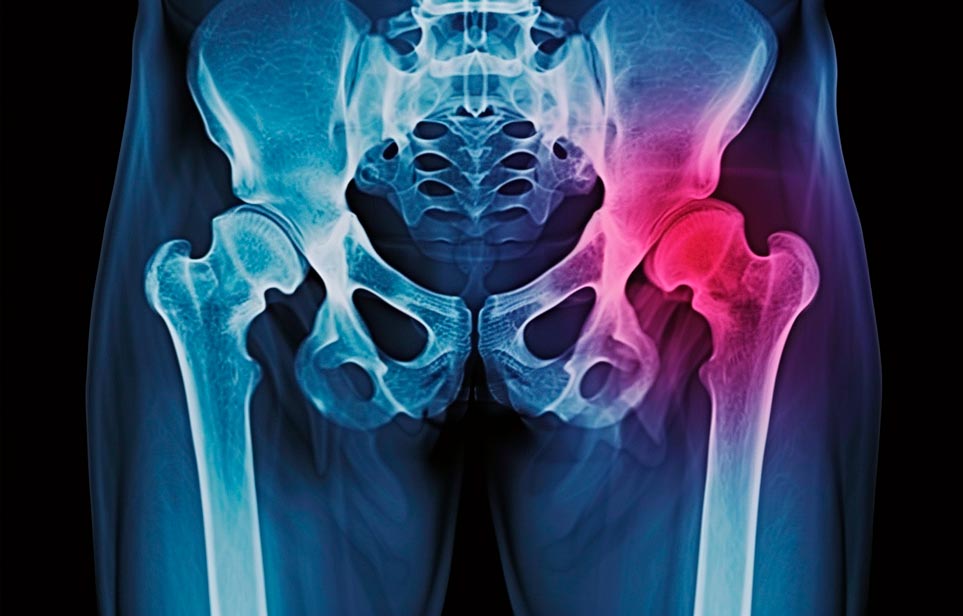

Реабилитация пожилых после перелома шейки бедра в Луганске

Эффективная и профессиональная реабилитация после перелома шейки бедра в Луганске осуществляется по демократичным ценам лучшими специалистами современной медицинской клиники «Заботливые люди» с применением персонального подхода к каждому пожилому человеку с такой тяжёлой травмой бедренной кости ноги. В процессе осуществления такой специализированной услуги все наши пациенты имеют возможность получения качественного и достойного обслуживания, эффективного восстановления. Лучший дом престарелых позаботиться о Вашем близком человеке.

Такая травма в большей части случаев возникает у граждан преклонного возраста. При её появлении на протяжении длительного времени сохраняются болевые и неприятные ощущения в области паха, при которых серьёзно ухудшается качество жизни, возникает множество последствий для его жизни и здоровья.